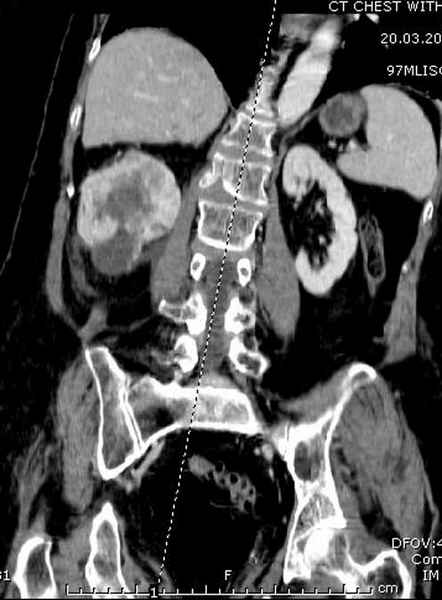

Со слов, больная ничем не болела, только последние 3 месяцев чувствовала боли в бедренной области. КТ брюшной полости подтвердил увеличенную правую почку. (5-6)